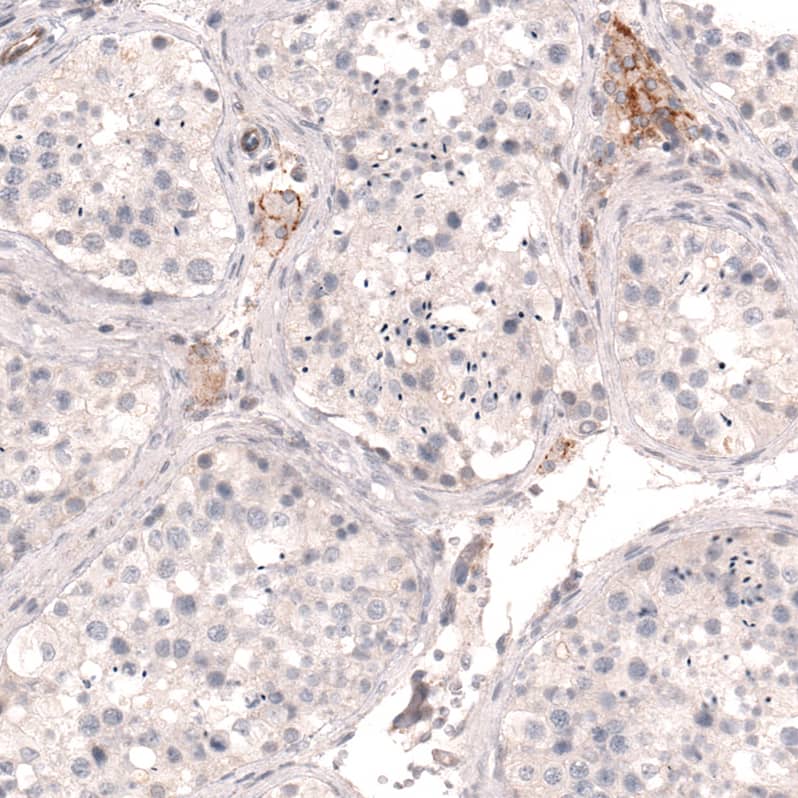

Orthogonal Strategies: Analysis in human kidney and skeletal muscle tissues using NBP3-44072 antibody. Corresponding THSD7A RNA-seq data are presented for the same tissues.

Staining of human kidney shows moderate membranous positivity in cells in glomeruli, as well as in a subset of renal tubules.

Staining of human testis shows moderate membranous positivity in Leydig cells.